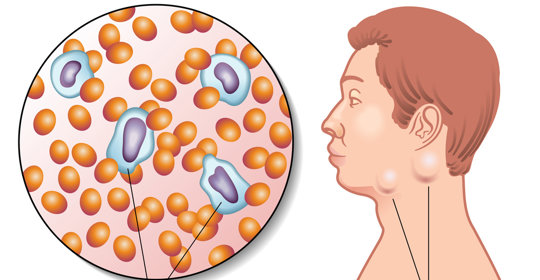

腦炎:A型流感與乙型流感的比較

腦炎後遺症:病因與治療

腦炎後遺症:主要致病原因及後期症狀

腦炎後遺症:急性腦炎、病毒性腦炎